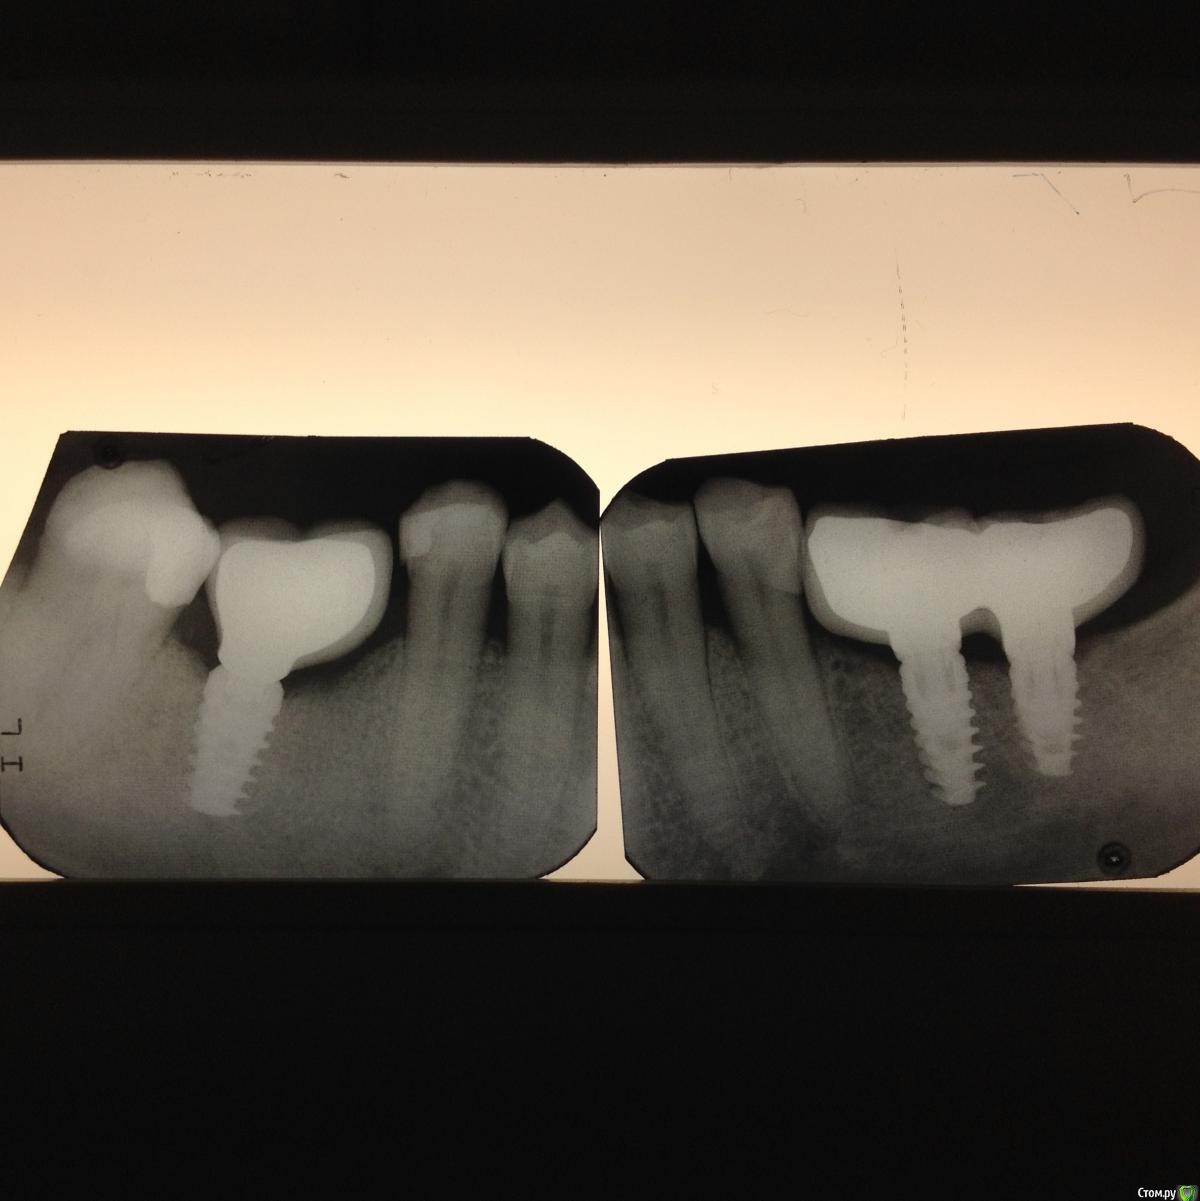

Freelancer1981 Опубликовано 14 марта, 2016 Поделиться Опубликовано 14 марта, 2016 Я не супер-специалист в имплантологии,но..почему не делали костную пластику? по снимку явно потеря вертикального обьема кости(скорее всего и по толщине),как следствие стоят импланты не того размера какие должны быть в боковом сегменте,мин размер 4 мм для боковых зубов(по ширине),несоответсвие оси импланти и окклюзионной плоскости-у вас почти консоль получился,ставили не по шаблону 100%+концевой дефект,антагонисты свои зубы- в вашей работе много рисков,долгосрочная выживаемость такой работы под сомнением. Ссылка на комментарий

Freelancer1981 Опубликовано 14 марта, 2016 Поделиться Опубликовано 14 марта, 2016 (изменено) Я не супер-специалист в имплантологии,но..почему не делали костную пластику? по снимку явно потеря вертикального обьема кости(скорее всего и по толщине),как следствие стоят импланты не того размера какие должны быть в боковом сегменте,мин размер 4 мм для боковых зубов(по ширине),несоответсвие оси импланти и окклюзионной плоскости-у вас почти консоль получился,ставили не по шаблону 100%+концевой дефект,антагонисты свои зубы- в вашей работе много рисков,долгосрочная выживаемость такой работы под сомнением.я имел ввиду 3 сегмент Изменено 14 марта, 2016 пользователем Freelancer1981 Ссылка на комментарий

Shakirbura Опубликовано 14 марта, 2016 Автор Поделиться Опубликовано 14 марта, 2016 размеры имплантов какие?4 сегмент 5х103 сегмент 4,2х10, 4,2х8В связке не продержатся? Ссылка на комментарий

Freelancer1981 Опубликовано 14 марта, 2016 Поделиться Опубликовано 14 марта, 2016 4 сегмент 5х103 сегмент 4,2х10, 4,2х8В связке не продержатся?хм..по снимку и не подумал бы,я думал меньше.почему не по шаблону ставили?на снимке коронки выглядят как китайская пагода,немного нервномерно нагрузка будет падать. Ссылка на комментарий

diesel87 Опубликовано 14 марта, 2016 Поделиться Опубликовано 14 марта, 2016 Мне казалось винтовая предпочтительнее, я не прав?Винтовая предпочтительнее на верхней челюсти и при расположении импланта по центру окклюзионной линии. 36 и 37 наверное бы выбрал инд абатменты с цементной фиксацией. Ссылка на комментарий